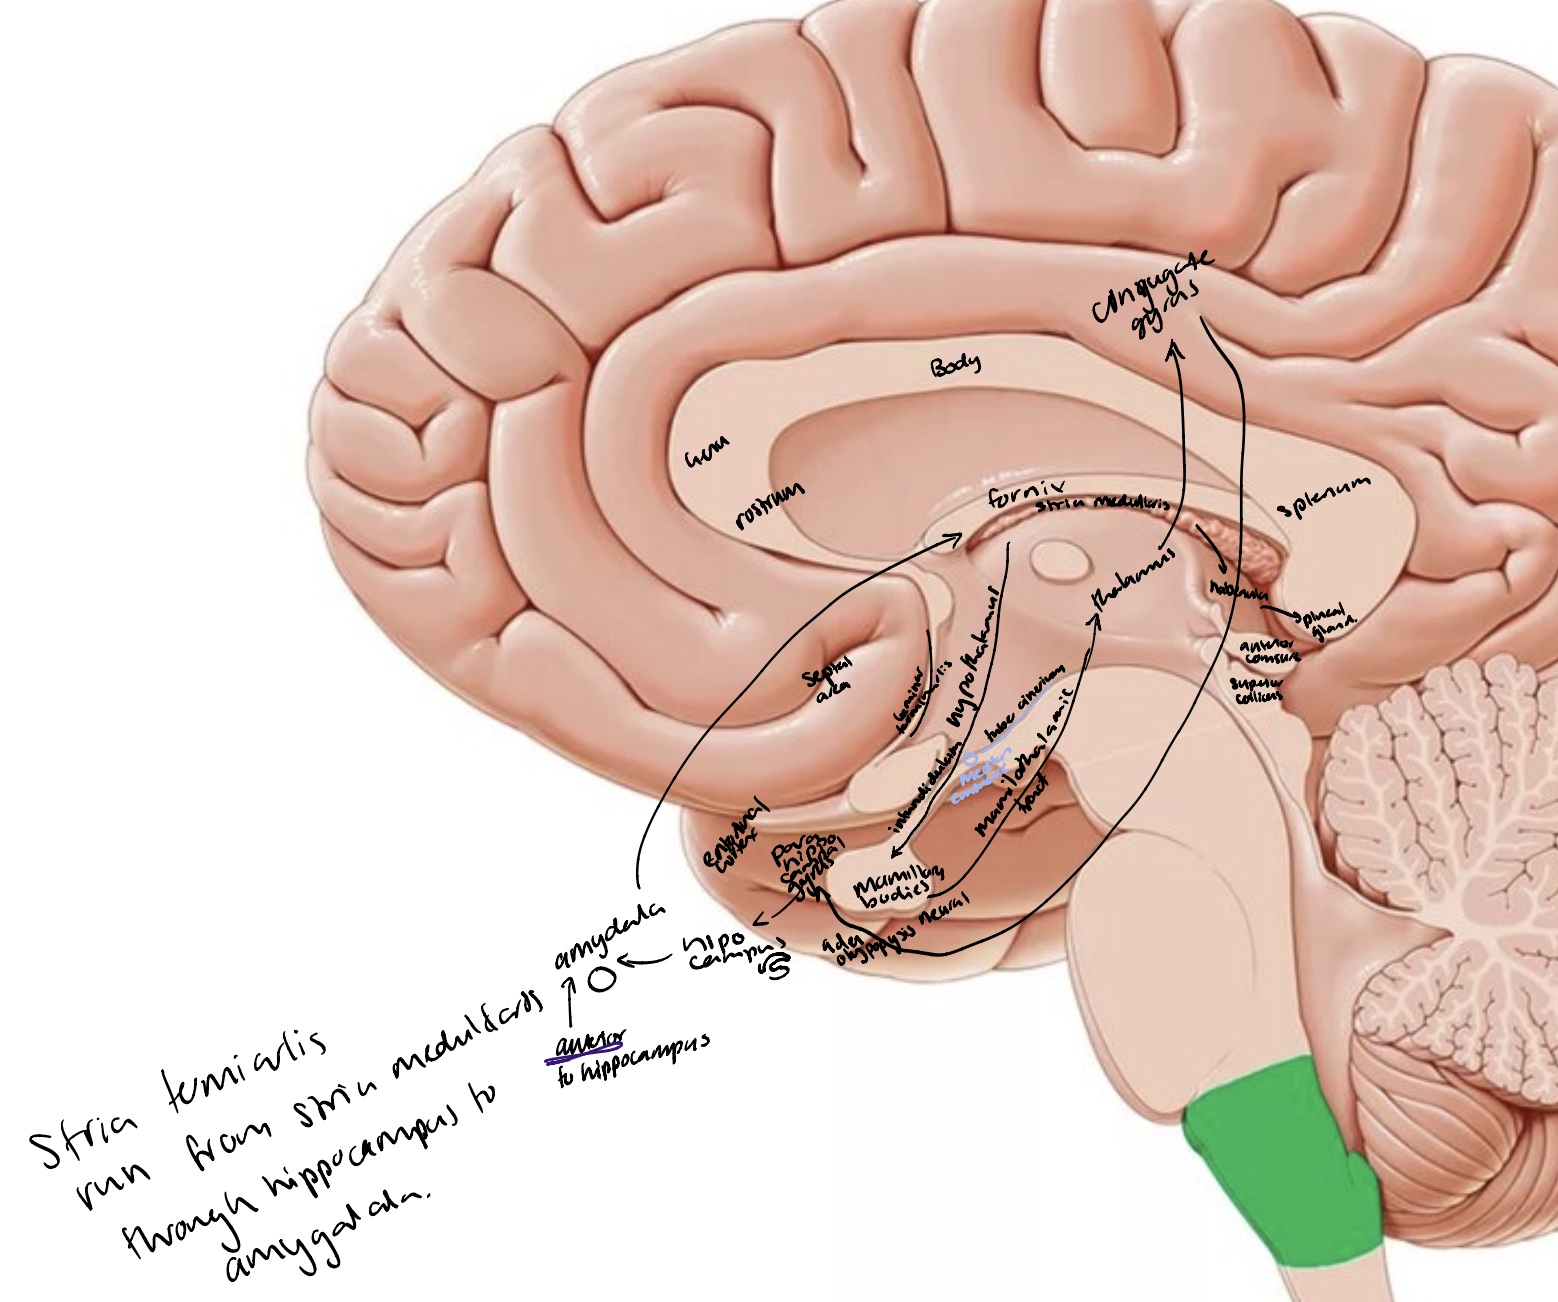

The limbic lobe

Cingulate gyrus

Parahippocampal gyrus (includes entorhinal cortex)

Hippocampal formation in the parahippocampal gyrus

Dentate gyrus

Subiculum

Septal nuclei in the septal area

Amygdala

Nucleus accumbens

Insula

Fibre tracts

Fornix

Mammillothalamic tract

Stria terminalis

Stria medullaris thalami

Other parts of the brain e.g., mammillary bodies (hypothalamus), nuclei in the thalamus, rhinencephalon (olfactory bulb, tract, striae.

The Papez Circuit

Parahippocampal gyrus → hippocampus → fimbriae → fornix → mammillary bodies (hypothalamus) → mammillothalamic tract → nuclei of thalamus → cingulate gyrus → parahippocampal gyrus/entorhinal cortex

Hypothalamus

Anterior commissure

Lamina terminalis

Thalamus

Optic chiasm

Infundibulum and pituitary gland

Tuber cinereum

Mammillary bodies

Cingulate gyrus

Fornix

Striae medullaris thalami

Pineal gland

Posterior commissure